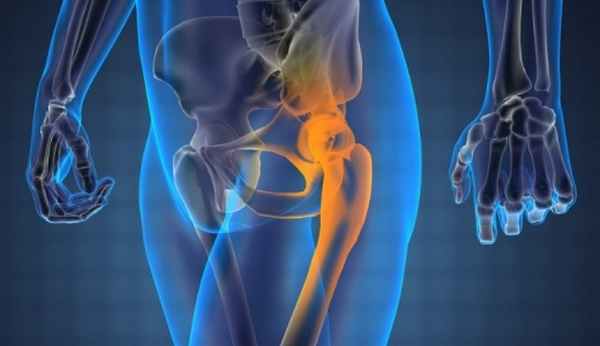

Саркомы костей могут локализоваться в любых костях скелета. Однако наиболее часто поражаются длинные трубчатые кости, преимущественно бедренная, большеберцовая и плечевая. Реже поражаются кости таза, лопатка и ребра.

Какие кости поражаются при раке

Принципиально возможно развитие метастаза в любой кости скелета, но чаще всего опухолевые клетки задерживаются в костях с лучшим кровоснабжением, где всегда есть достаточное питание для продолжения неуправляемого деления. Очень редко метастазы образуются в мелких косточках кисти и стопы, но часты в обильно пронизанных сосудистой сетью костях таза, позвонках и ребрах, нередко поражают кости черепа, за исключением лицевого скелета. Наибольшую опасность для пациента несёт опухолевое поражение позвонков и трубчатых костей конечностей, когда в месте деструкции при обычной нагрузке случается перелом, лишающий возможности двигаться, а при патологическом переломе шейного позвонка высока вероятность паралича из-за сдавления спинного мозга отломками разрушенной опухолью кости.